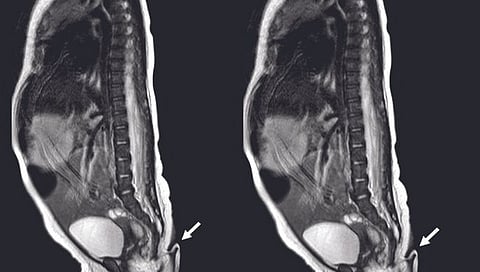

तिला जन्मतःच शेपूट होती. ही शेपूट 5.7 सेंटीमीटर लांब व 3 ते 4 मि.मी. रुंद होती. या शेपटीला थोडे थोडे केसदेखील होते, असे डॉक्टरांनी म्हटले आहे. 'जर्नल ऑफ पीडियाट्रिक सर्जरी' मध्ये या प्रकरणाबाबत माहिती दिली आहे. चिमुकलीची आई जेव्हा गर्भवती होती तेव्हा तिला कोणत्याही प्रकारचा त्रास जाणवला नाही. तिच्या मेडिकल हिस्ट्रीमध्ये कोणताही संसर्ग आणि रेडिएशनचा इतिहास नाही. त्यांना आधीही एक मुलगा झाला होता. मात्र, तो सर्वसामान्य व स्वस्थ आहे.

मात्र, मुलीचा जन्मतःच शेपूट असल्याने डॉक्टरही हैराण झाले आहेत. शेपटी आढळल्यानंतर मुलीची तपासणी करण्यात आली. तेव्हा तो केवळ मांसाचा गोळा असल्याचे समोर आले. तिथे एकही हाड नव्हते. शेपटी मऊ होती, त्वचेने झाकलेली होती आणि त्यावर हलके केस होते. शेपटी हलवल्यानंतर कोणतीही वेदना होत नव्हती, असे निरीक्षण पोलिसांनी नोंदवलं आहे. सर्व चाचण्या केल्यानंतर एका छोट्याशा ऑपरेशननंतर मुलीच्या शरीरातून शेपटी काढून टाकण्यात आली. तसेच, रुग्णालयातून डिस्चार्ज दिल्यानंतर मुलीची प्रकृती स्थिर असून अद्याप कोणतीही समस्या आली नाही.